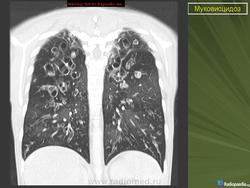

При тщательном обследовании обнаруживается учащенное дыхание, увеличение переднезаднего размера грудной клетки и слабо выраженное, но стойкое втяжение нижних межреберных мышц. Аускультативные патологические признаки могут вообще не выявляться или присутствовать в виде сухих и влажных мелко- и крупнопузырчатых хрипов. На рентгенограмме органов грудной полости выявляют уплотнение стенок бронхов, а также различной степени уплотнение или повышенную воздушность легочной ткани. Могут развиваться ателектазы в сегментах и долях легких, причем поражение правой верхней доли относится к диагностически значимым признакам муковисцидоза.

• ухудшение физикальной и рентгенологической картины в легких;

- Рентгенография органов грудной клетки в прямой и правой боковой проекциях.

• новые рентгенологические изменения в легких (инфильтраты, ателектазы, сливающиеся, гомогенные затемнения или параллельные линейные тени);